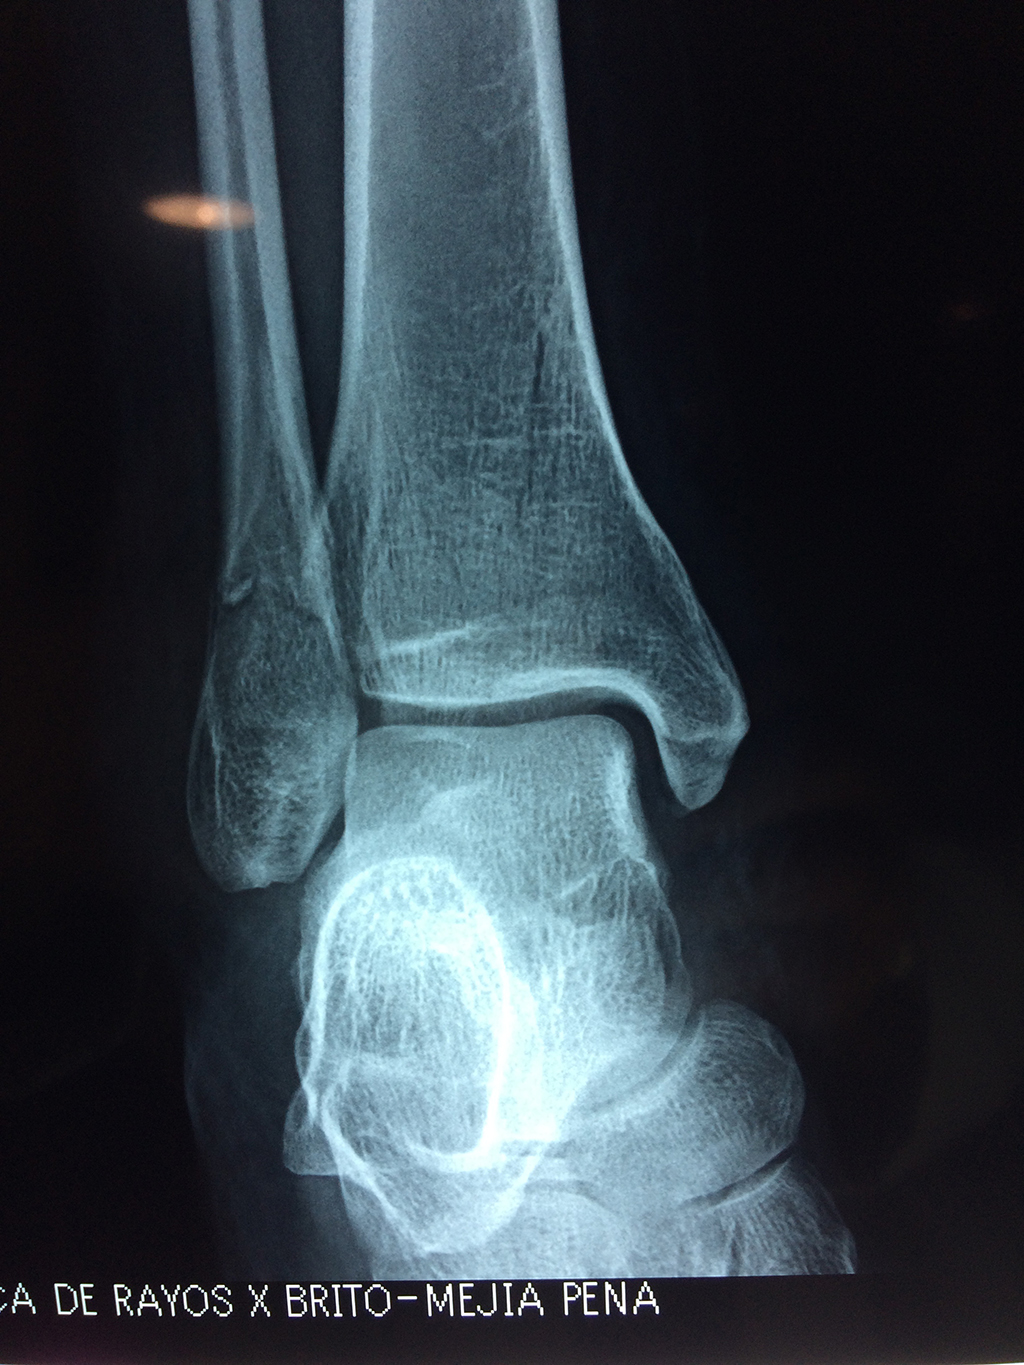

Una fractura de tobillo es la rotura de uno o más de los huesos del tobillo. Estas fracturas pueden ser:

- Completas (el hueso está perforado y está en 2 partes).

- Producirse en uno o ambos lados del tobillo.

- La fractura se extiende hasta la articulación del tobillo (fractura intra-articular).